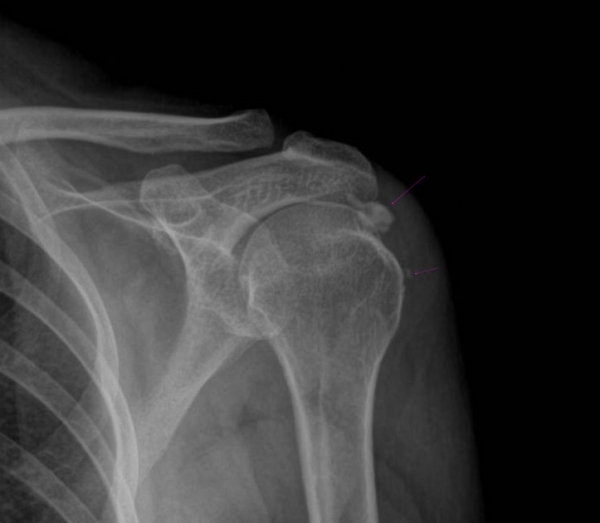

¹æ»ç¼± °Ë»ç :  ÃÊÁø ½Ã ¹æ»ç¼± °Ë»ç¿¡¼­ ¾çÃø ±Ø»ó°Ç°ú °ß°©Çϱٰǿ¡ Å« ¼®È¸°¡ °üÂûµÈ´Ù(»çÁø 8. 9).

Ä¡·á ÈÄ ¾à 1´Þ ÈÄ¿¡ ÃßÀû °Ë»çÇÑ »çÁø¿¡¼­  ¿ìÃø ±Ø»ó°Ç ¼®È¸´Â °ÅÀÇ ¼Ò½ÇµÈ ¸ð½ÀÀ̰í

ÁÂÃø ±Ø»ó°ÇÀÇ ¼®È¸´Â ¸¹ÀÌ ÁÙ¾îµç ¸ð½ÀÀÌ´Ù(»çÁø  10. 11).